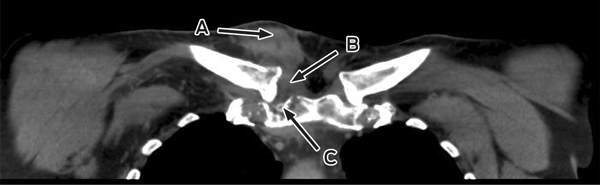

Despite ongoing cephazolin therapy, the patient developed increasing pain over the right sternoclavicular joint. Computed tomography imaging demonstrated changes consistent with a joint effusion, localised oedema, septic arthritis and osteomyelitis of the upper manubrium and medial right clavicle (Box 2). After initial conservative management without symptom resolution, surgical debridement was performed, and culture of the excised tissue grew MDR E. coli. The patient subsequently complained of lumbar back pain, and MRI of the lumbar spine showed changes consistent with an epidural abscess together with immediately adjacent discitis and osteomyelitis at the L4–5 vertebrae (Box 3). An orthopaedic consultation recommended conservative management, and the patient’s primary care was transferred to infectious diseases physicians. After 5 weeks of intravenous cephazolin therapy in hospital, he was discharged with a treatment regimen of intravenous ceftriaxone 2 g daily delivered by an elastomeric infusion device (Baxter) managed by the home-based acute care service.